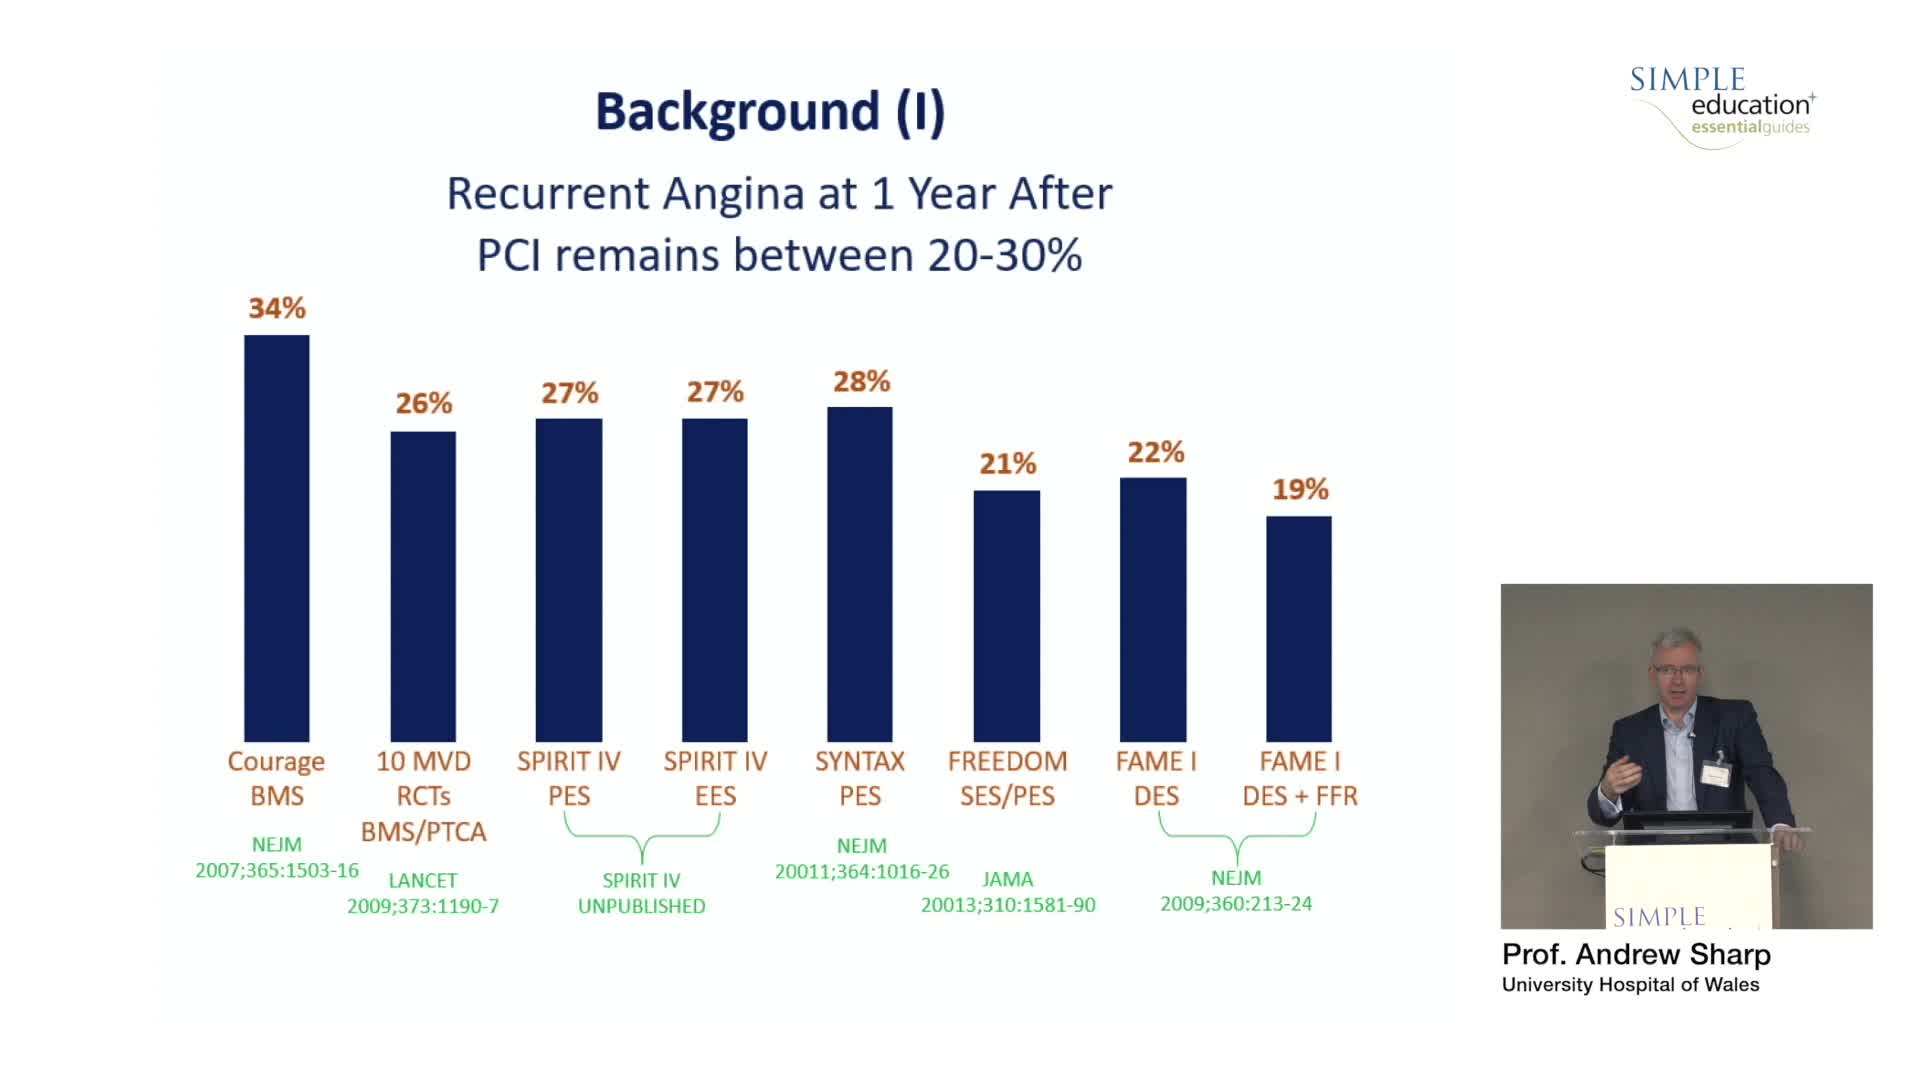

Best practices and personalised medicine in complex PCI - Prof Javier Escaned

Essential steps for physiology-based PCI planning and guidance - Dr Allen Jeremias

Revascularisation in stable angina: a contemporary perspective - Dr Rasha Al-Lamee